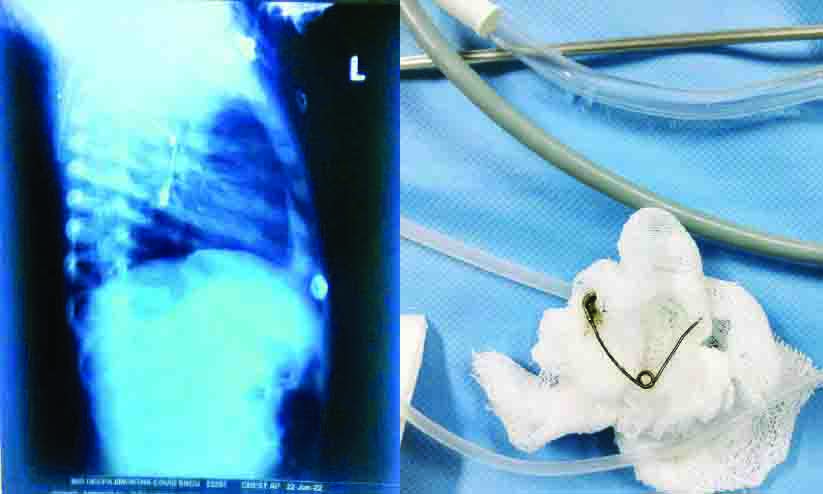

മുളങ്കുന്നത്തുകാവ്: ഗവ. മെഡിക്കൽ കോളജിൽ എട്ടു മാസം പ്രായമുള്ള ആൺകുഞ്ഞിന്റെ അന്നനാളത്തിൽ കുടുങ്ങിയ സേഫ്റ്റി പിൻ...

പിന്നിന്െറ തലഭാഗം ഒടിഞ്ഞ് ആമാശയത്തില് കുടുങ്ങി